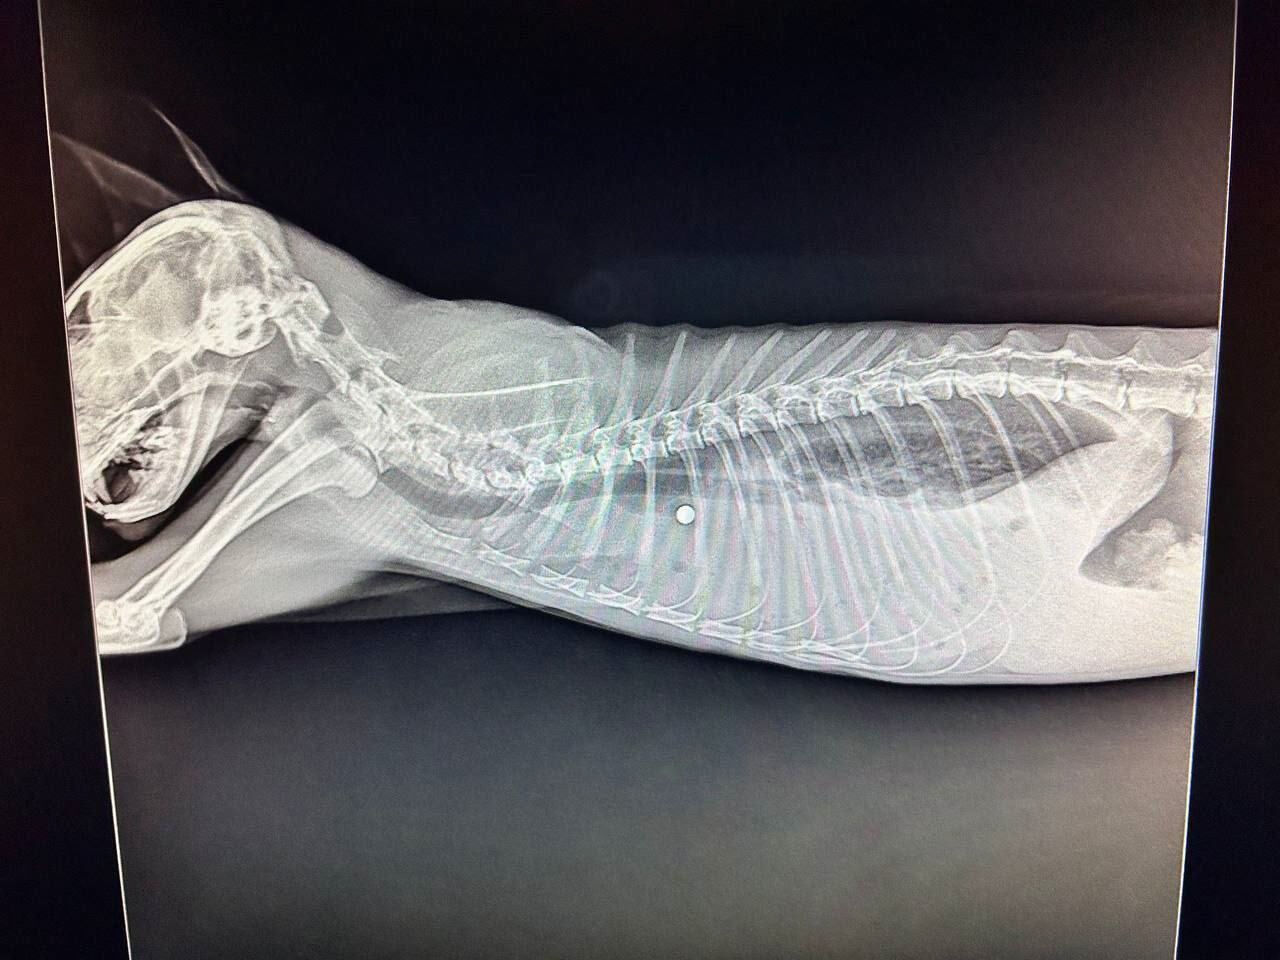

Пуля угодила в тело домашнего кота после нападения неизвестного с "травматом" в Приморском крае. В ситуации разбираются правоохранители.

Правоохранители узнали о случившемся во время мониторинга средств массовой информации. Там сообщалось, что в районе улицы Уютной в селе Вольно-Надеждинское неизвестный напал на кота. Он выстрелил в домашнее животное из травматического оружия, а затем скрылся с места происшествия.